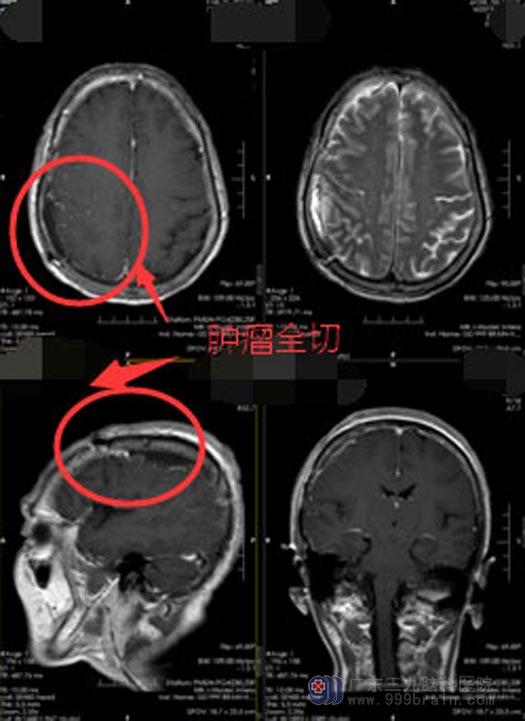

12月4日,神经外五科手术团队为关阿姨实施了“右顶部脑膜瘤切除术”,手术利用显微镜仔细分离肿瘤与软脑膜,完整切除肿瘤,并去除部分受到肿瘤侵犯的硬脑膜,手术过程非常顺利。

术后,关阿姨头痛症状已大大缓解,肢体活动有力,未出现术后并发症。